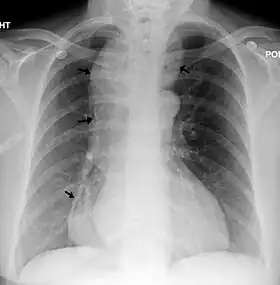

Une radiographie pulmonaire montrant une achalasie (les flèches pointent vers le contour de l'œsophage massivement dilaté)